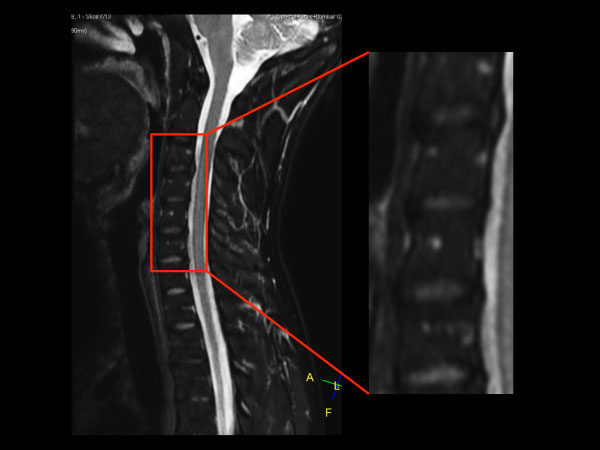

Premium Fat-free Pediatric Spine imaging

Phoenix Children Hospital, USA